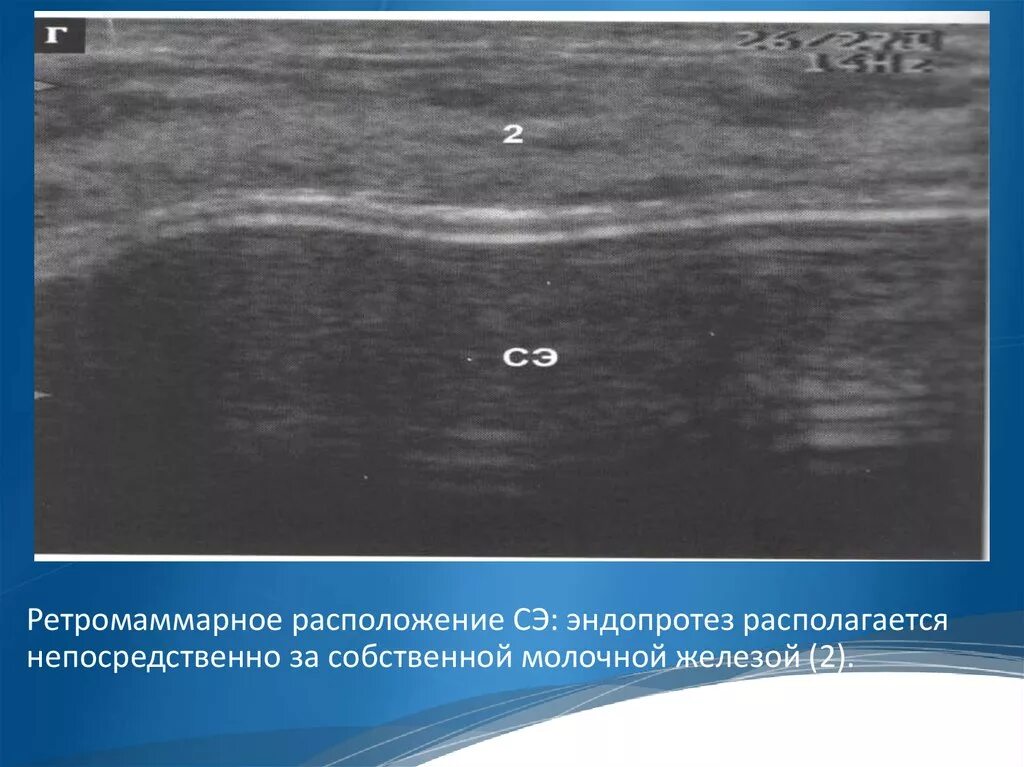

Узи молочных киров